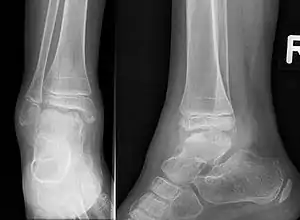

| Trevor disease in a 9 yr old girl: Talus | |

This disorder is rare, and is characterised by an asymmetrical limb deformity due to localized overgrowth of cartilage, histologically resembling osteochondroma. It is believed to affect the limb bud in early fetal life. The condition occurs mostly in the ankle or knee region and it is always confined to a single limb. This usually involves only the lower extremities and on medial side of the epiphysis. It is named after researcher David Trevor.[1]

Trevor disease was first described by the French surgeon Albert Mouchet and J. Belot in 1926. In 1956, the name "dysplasia epiphysealis hemimelica" was proposed by Fairbank.[1] The usual symptoms are the appearance of an osseous protuberance, on one side of the knee, ankle or foot joint which gradually increases Radiologically,[14] the condition shows a nonuniformity of growth and multiple unconnected ossification centers around the epiphyses.[8]